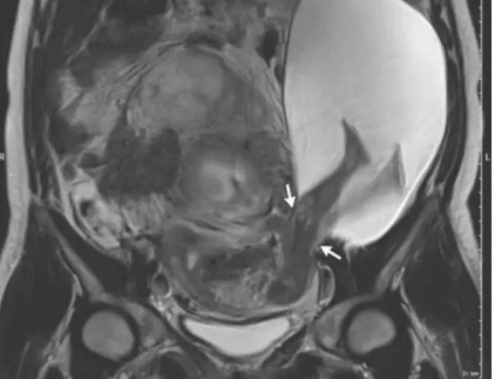

O bebê, então com aproximadamente 25 semanas, rompeu a parede uterina e esticou as pernas na cavidade abdominal da mãe. Ela, segundo a publicação, não relatava qualquer sintoma de dor ou estranheza.

Uma ressonância magnética indicou que o ‘buraco’ no útero era de 2,5 centímetros.